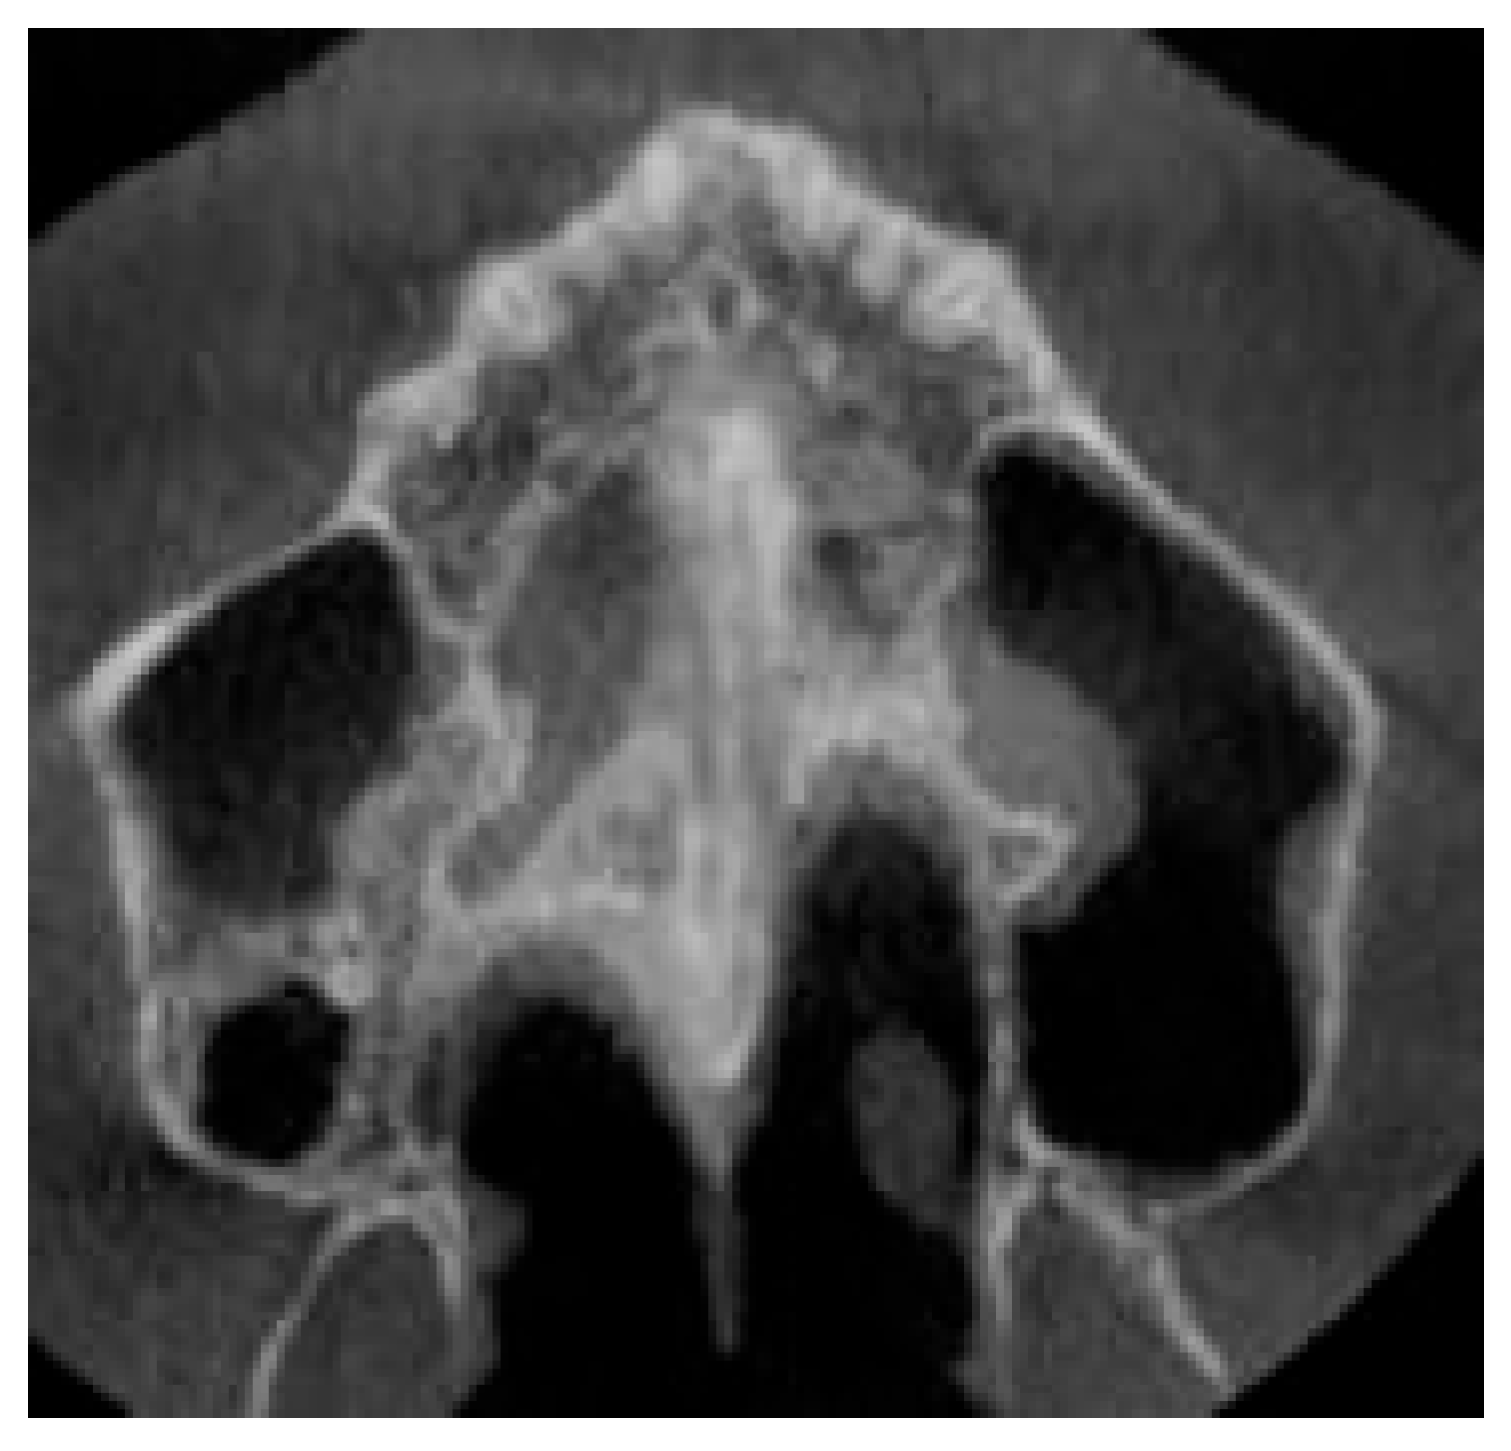

2.9.1. Qualitative Evaluation of Maxillary Expansion on Cone Beam Computed Tomography

3.2. Qualitative Evaluation of Maxillary Expansion on Cone Beam Computed Tomography